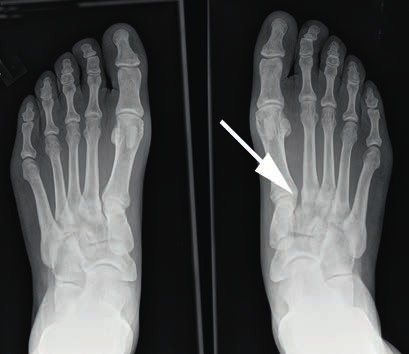

- Bei einer Grad-II-Verletzung findet sich in den Röntgenaufnahmen unter Belastung eine Diastase zwischen dem I. und II. Mittelfußknochen von 2 bis 5 mm. Die Seitenaufnahme des Fußes im Seitenvergleich ist unauffällig (Abb. 3). Im MRT kann eine partielle Ruptur der Bänder nachgewiesen werden. Nicht selten finden sich ab Grad-II-Verletzungen im MRT Ödeme der subchondralen Spongiosa der angrenzenden Gelenkflächen.

Bei Athleten tritt eine Verletzung des Lisfranc-Bandkomplexes typischerweise auf, wenn der Fuß bei gleichzeitiger Plantarflexion und leichter Rotation axial belast et wird 43 44. Die Zerreißung des Lisfranc-Bandkomplexes führt zu einer tarsometatarsalen Dehiszenz mit Dislokation der Metatarsale-II-Basis nach dorsal 45. Nunley und Vertullo (2002) 46 gehen in ihren Untersuchungen davon aus, dass es bei der Grad-I-Verletzung lediglich zu einer Distorsion des Lisfranc’schen Bandes in Verbindung mit einer Verletzung der Gelenkkapsel kommt. Aufgrund des in sich noch stabilen Kapselbandkomplexes finden sich normale Belastungsaufnahmen; die Verletzung der dorsalen Bandanteile lässt sich jedoch kernspintomografisch nachweisen 47. Bei der Grad-II-Verletzung kommt es zusätzlich zu einer vollständigen Zerreißung der dorsalen Bandanteile. Radiologisch zeigt sich dies durch das Auseinanderweichen von Os metatarsale I und II auf den Röntgenaufnahmen unter Belastung. Da die plantaren Kapselbandanteile intakt bleiben, kommt es jedoch zu keinem Absinken des Längsgewölbes in der Seitenaufnahme. Bei Grad-III-Verletzungen liegt eine komplette Zerreißung der dorsalen und plantaren Kapselbandstrukturen mit einem instabilen ersten Tarsometatarsalgelenk vor. Dies zeigt sich radiologisch durch ein Absinken des Längsgewölbes 48.